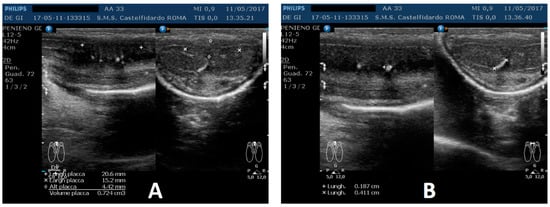

A penile Doppler ultrasound was performed (alprostadil 10 mcg). The penile deformity consisted of dorsal penile curvature (30 degrees). The arterial flow of the cavernous arteries and the end-diastolic velocity were normal: peak-systolic velocity = 96 cm/s (left) and 94 cm/s (right); end-diastolic velocity = 0 cm/s (on both sides). The plaque was located in the middle of the penis, its ultrasound aspect was iso-hypoechoic, and it measured 20.6 × 15.2 × 4.42 mm (724 mm3 = volume); within the plaque, there were some small calcifications, the largest of which measured 1.9 × 4.1 mm (Figure 9).

Figure 9. Ultrasonography of the penis before therapy (longitudinal and axial views). (A) Entire plaque; (B) the largest calcification.